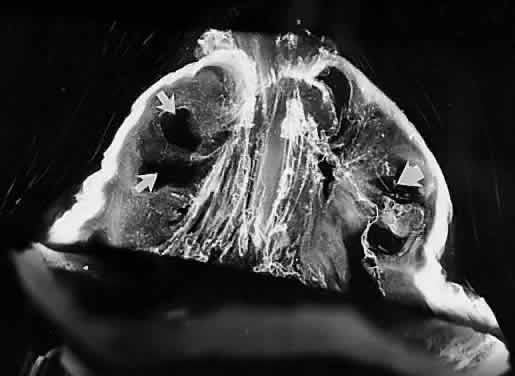

Fig. 16. Vitreoretinal interface in youth. A: Dark-field microscopy of the posterior vitreous in a 14-year-old boy. The sclera, choroid, and retina were dissected off the corpus vitreus, which remains attached to the anterior segment. In contrast to adults, there is an extra layer of tissue that remained adherent to the posterior vitreous cortex when the retina was dissected off. The white arrow indicates the location of the fovea. The circular structure below this location is the prepapillary hole in the posterior vitreous cortex. Emanating from this hole are linear, branching structures (black arrows) that correspond to the location of the retinal vessels. B: Scanning electron microscopy of the tissue described in (A) demonstrates many round structures adherent to the posterior aspect of the tissue. Bar = 10 μm. C: Higher magnification showing the attachment of one of these round structures. There appears to be an indentation or hole on the posterior aspect of this structure. Bar = 1 μm. D: Transmission electron microscopy of this specimen identifies this tissue as the internal limiting lamina (ILL) of the retina attached to the posterior vitreous cortex. The round structures are identified as the inner portion of Müller cells that remained adherent to the posterior aspect of the ILL, with a hole on the posterior aspect of the inner portion of the Müller cell where it was torn away from the rest of the cell body (×20,800). (From Sebag J. Age-related differences in the human vitreoretinal interface. Arch Ophthalmol 109:966, 1991, with permission)